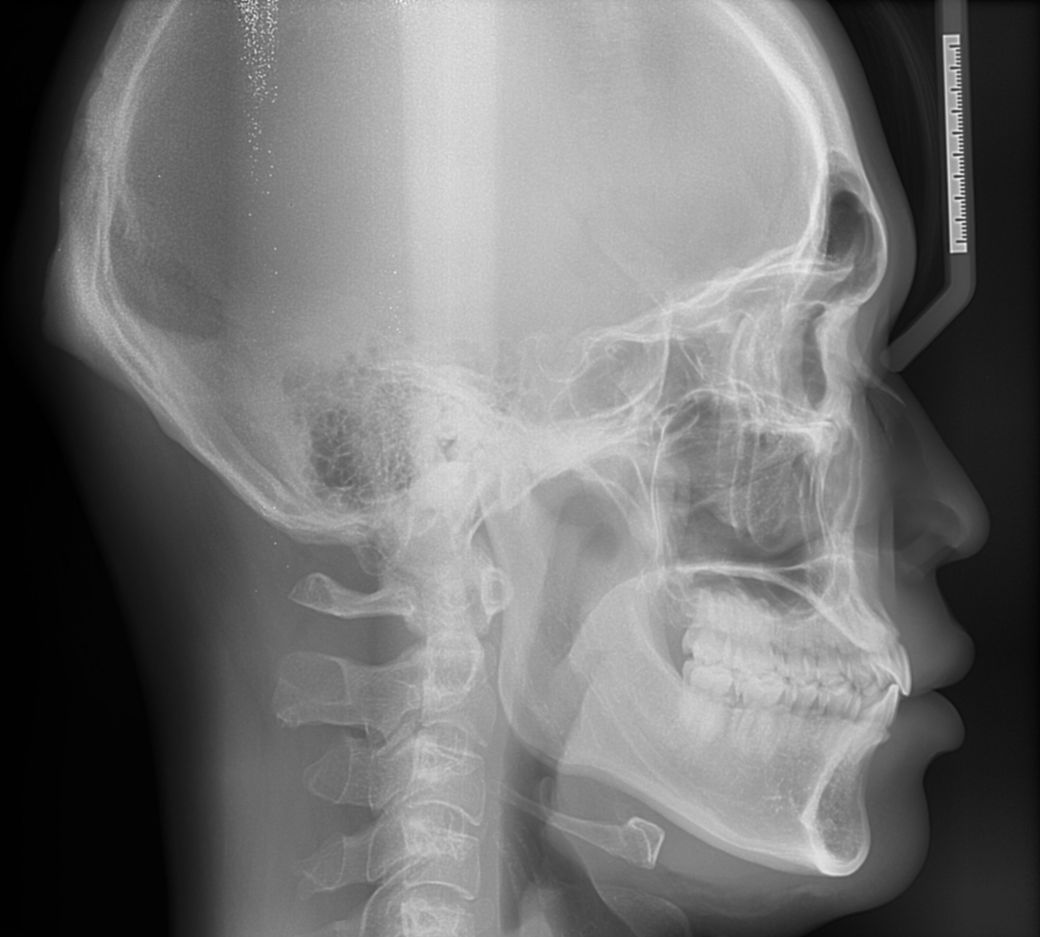

사진과 xray사진상 주걱턱인가요?

치과에서 정밀검사때 의사님이 분석한 데이터 결과를 보여주셨는데 턱길이가 평균치보다 길다고하는데

이거 주걱턱인가요?수술이 필요한건가요?

cephalo PA 분석을 하여 기준치 이상의 경우 이를 주걱턱 또는 하악골돌출 등으로 표현합니다.

분석을 해봐야 알겠지만, 눈대중으로 보았을 때는 큰 문제는 없어보입니다.

하악 길이가 긴 것과 또 주걱턱은 다른 개념이므로 자세한 진단을 원하시면

일반인들이 알기에는 여러가지 지표를 모두 알기 힘들지만 쉽게 설명 드릴 수 있는 부분은 맨 아래 사진에서 코 끝과 턱 끝의 연조직을 연결했을 때 그 선을 기준으로 입술이 얼마나 튀어나왔는지 기준으로 판단하기도 합니다. 현재 계측점이 정확히 찍혀 있지 않으나 상악에 비해 하악이 발달 한 것은 맞습니다.

다만 주걱턱이라고 하기에는 심미적으로 턱이 많이 나와 있지 않아 양악을 하거나 교정의 필요성은 특별히 많지 않습니다. 교합도 좋아 보이구요.

사진상으로는 주걱턱이거나 그렇진 않아 보입니다. 평균보다 하악턱이 길다고 모두 주걱턱은 아니세요.

교정분석을 통해서 기준선보다 하악턱이 전방으로 나오게 되면 주걱턱이라고 보시면될것같습니다. 작성자님께서는 x-ray사진으로 본다면 주걱턱은 아니신거 같습니다.